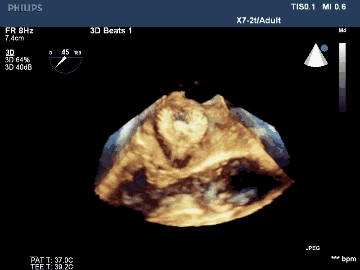

術后TEE三維重建影像示封堵器位置佳,封堵完全